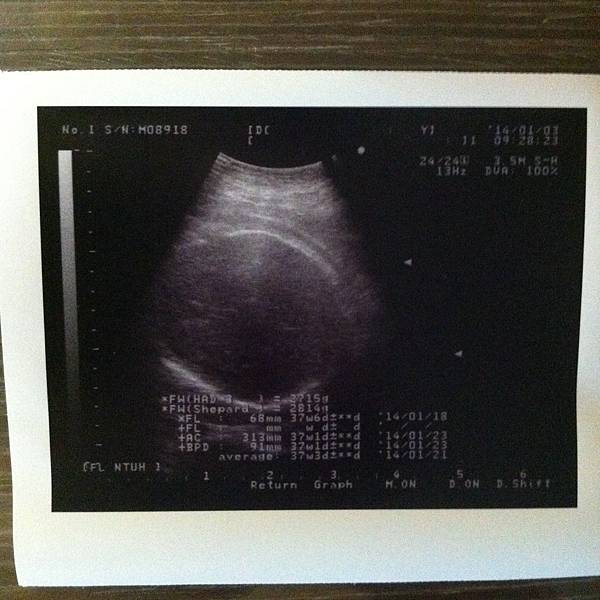

37週的寶寶已經2800克左右了,已經達標可以準備出來了!